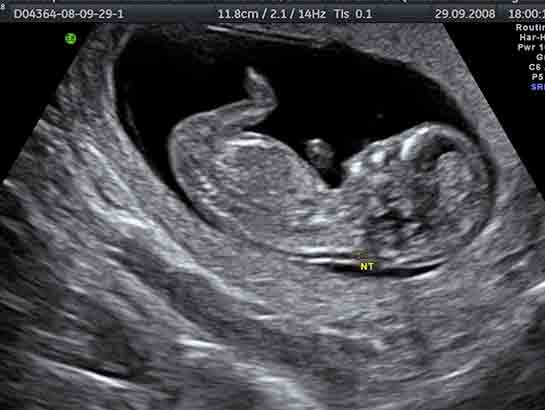

11 14 Testi Ikili Test Down Sendromu Testi Ve Ense Kalinligi Nt Olcumu Youtube